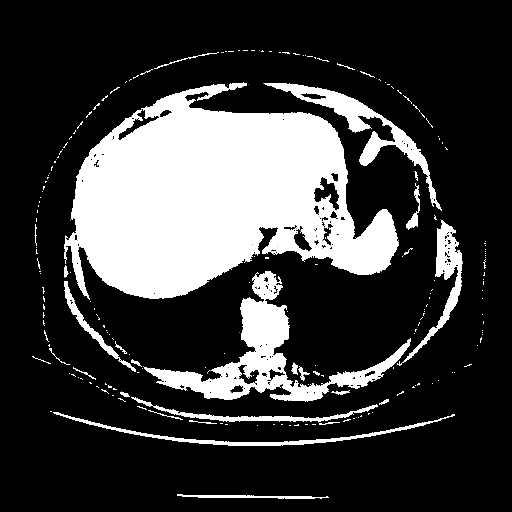

Original NATIVE CT scan (input)

Full window (WL 1023.5, WW 4095 β†’ Low βˆ’1024, High +3071)

Actual HU range: [-1024.0, 3071.0]